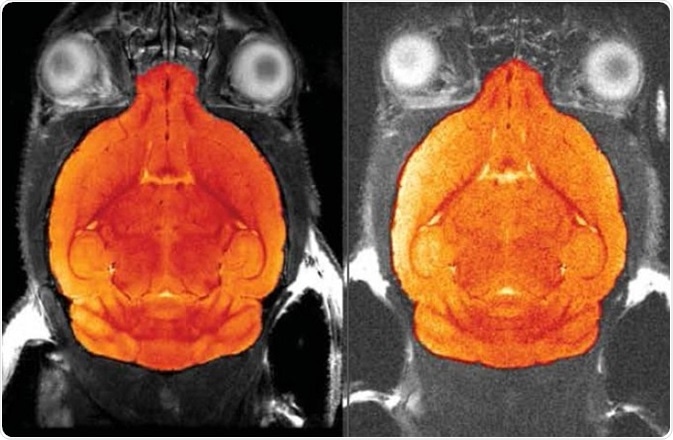

Comparison of 1H four channel phased array receive-only MRI CryoProbe with room temperature phased-array coil

The significant signal gain reduces the scan time considerably without compromising the resolution. The four channel phased array MRI CryoProbe (left image) can achieve a signal-to-noise gain of 2.6 compared to a room temperature four channel phased array coil (right image).

Comparison of 1H four channel phased array receive-only MRI CryoProbe with room temperature phased-array coil. Image Credit: Bruker BioSpin Group